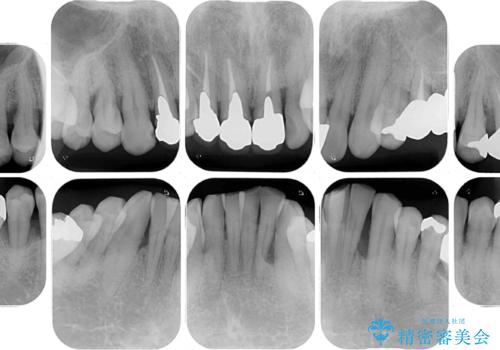

臼歯部には歯周ポケットのある箇所が散見されましたが、まずは前歯を治療したいとのことで、治療を進めました。

ディープバイトにより臼歯部に負担のかかる咬合であったので、補綴治療後には、矯正治療の後戻り防止もかねて、睡眠時にマウスピースを装着するように指示しました。